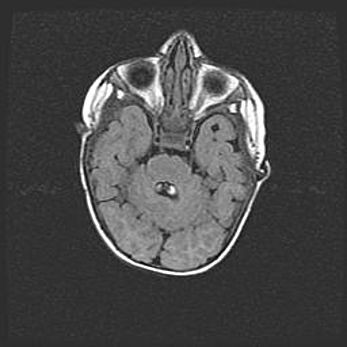

Мальформация Денди-Уокера. Киста задней черепной ямки.

Агенезия мозолистого тела.

Возраст: 2,5 месяца

Вес: 2420 г

Пол: женский

Окружность головы: 37 см

Срок гестации: 32 недели

Мальформация Денди—Уокера — редкий вид патологии ЦНС, представляющий собой врожденный порок развития каудального отдела ствола и червя мозжечка, ведущий к неполному раскрытию срединной (Мажанди) и латеральных (Лушка) апертур IV желудочка мозга. Для этогно синдрома характерна триада симптомов: гипотрофия червя мозжечка и/или полушарий мозжечка, кисты задней черепной ямки, гидроцефалия различной степени. В 70% случаев порок сочетается и с другими аномалиями головного мозга, в частности с агенезией мозолистого тела.